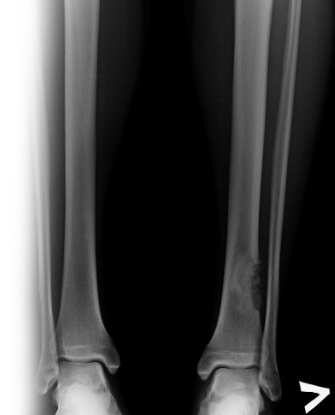

Рентгенография берцовых костей

Рентгенография большой берцовой и малой берцовой костей – важный метод прицельного исследования, который позволяет оценить состояние берцовых костей.

Диагностическая услуга выполняется в двух проекциях.

Рентген позволяет исключить патологию берцовых костей костно-травматического, опухолевого и воспалительного генеза.